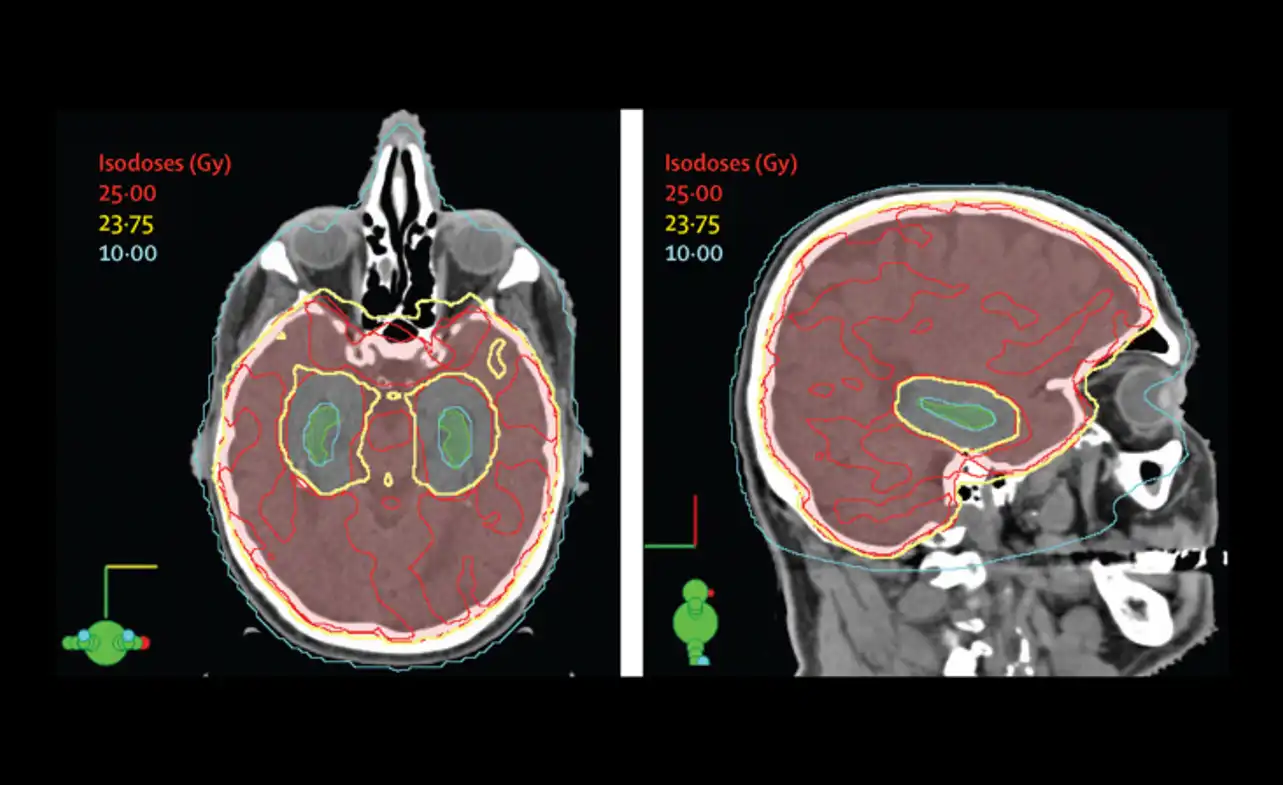

Radiation Therapy Techniques for Preventing Brain Metastases

Radiation therapy is a common strategy for preventing brain metastases in cancer patients. Prophylactic cranial irradiation can be delivered using various techniques, each with its benefits and limitations. The two most commonly used radiation therapy techniques for prophylactic cranial irradiation are:

Whole-brain radiation therapy (WBRT) WBRT delivers radiation to the entire brain, including areas unaffected by the cancer. It is a simple and effective approach to prophylactic cranial irradiation, but it can cause side effects like fatigue, hair loss, and cognitive impairment.

Intensity-modulated radiation therapy (IMRT) IMRT delivers more precise radiation to the brain, targeting regions most at risk for metastasis. This technique typically produces fewer side effects, but it requires more planning and monitoring to ensure accurate delivery.

Other radiation therapy techniques that may be used for prophylactic cranial irradiation include stereotactic radiosurgery and hippocampal sparing. These approaches are designed to be even more precise than IMRT, targeting specific areas of the brain while sparing healthy tissue. However, they are still being studied for their effectiveness in preventing brain metastases.

Ultimately, the choice of radiation therapy technique for prophylactic cranial irradiation will depend on various factors, such as the type and stage of cancer, the patient’s overall health, and individualized treatment plans. Consultation with a radiation oncologist is necessary to determine the best approach for each patient.